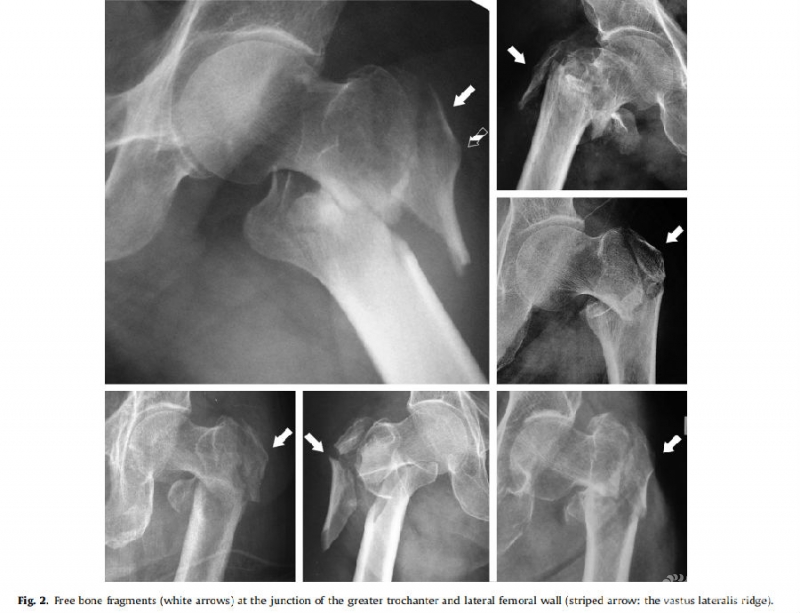

图2. 大转子与外侧壁交界处的游离骨折块示意图(白色箭头)

结果:10例(10%)发生内固定失败。单因素分析发现大转子和外侧壁连接处存在游离骨块(21.25;95%CI,4.31-104.67;p<0.001)和外侧壁的横行骨折线(原发或医源性)(OR, 5.36;95%CI,1.29-22.30;p=0.021)为内固定失败的危险因素。多因素回归分析发现,大转子和外侧壁连接处存在游离骨块(OR,16.05;95%CI,3.06-84.23;p= 0.001)是内固定失败的危险因素。

结论:股骨大转子与外侧壁交界处存在游离骨块和外侧壁横行骨折线是股骨转子间骨折伴外侧壁骨折内固定失败的危险因素。股骨外侧壁的完整性与股骨转子间骨折的预后相关。股骨转子间骨折合并外侧壁骨折时,可能需要重建股骨外侧壁。